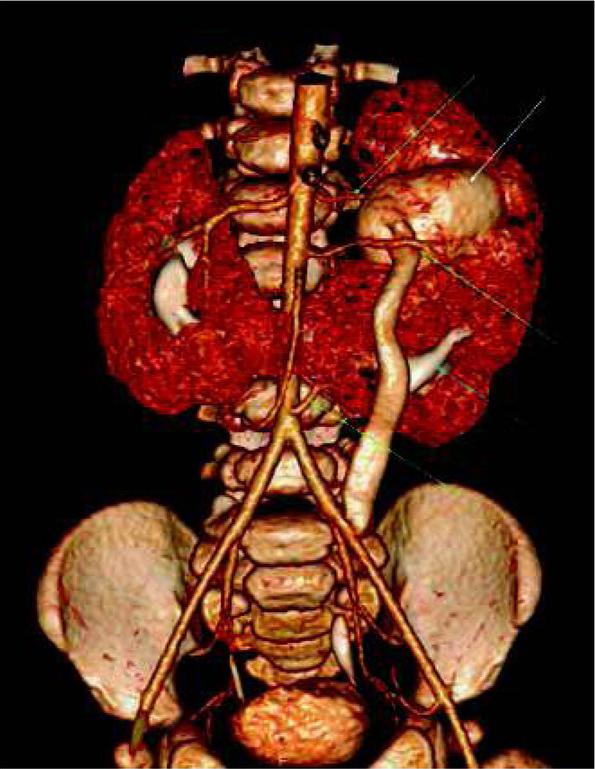

Combination of vascular and excretory phases (Protocol 3) provides the most complex visualization of the urinary system. It allows to asses abnormalities of the collecting system, with additional information about renal vascularity and general renal anatomy. It appears very useful especially before planned surgical intervention, e.g. heminephrectomy in duplicated collecting systems, where renal vessels and borders between both parts of the kidney should be evaluated (fig. 2). Vascular phase in this technique is not a “pure” CT-angiography, and it allows to assess renal parenchyma as well - higher heart rates in children will early enhance renal parenchyma in cortico-medullary phase [13]. Also, this protocol allows to detect crossing vessels as the cause of hydronephrosis [14, 15]. In comparison to other protocols, Protocol 3 will directly visualize the additional renal artery crossing and compressing the proximal ureter (fig. 3).

Volume reconstruction after one-phase split-bolus CTU performed in a 7-month-old boy with duplication of the collecting system in the left part of the horseshoe kidney (white and blue arrows), with rotation and hydronephrosis of the upper system (white arrow) and a megaureter. There are three renal arteries on the left side (green arrows), and the middle one crosses and compresses proximal part of the left upper ureter.

Ryc. 3. Rekonstrukcja objętościowa jednofazowej Uro-TK z podzielonym bolusem środka kontrastowego wykonanej u 7-miesięcznego chłopca ze zdwojeniem lewej części nerki podkowiastej (białe i niebieskie strzałki), z rotacją i wodonerczem górnego układu (biała strzałka) oraz moczowodem olbrzymim. Badanie wykazało obecność trzech tętnic nerkowych po stronie lewej (zielone strzałki), z których środkowa krzyżuje i uciska moczowód górnego układu.